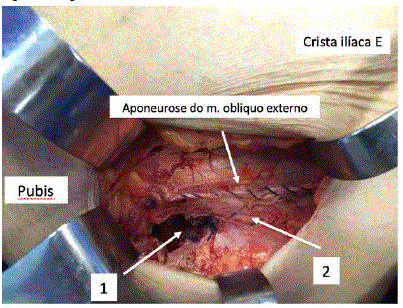

Mulher, 80 anos de idade, com história de dor e abaulamento na região inguino-crural esquerda conforme ilustra a figura a seguir.

Foi submetida a tratamento operatório conforme demonstrado na figura a seguir. Cite as estruturas anatômicas assinaladas: